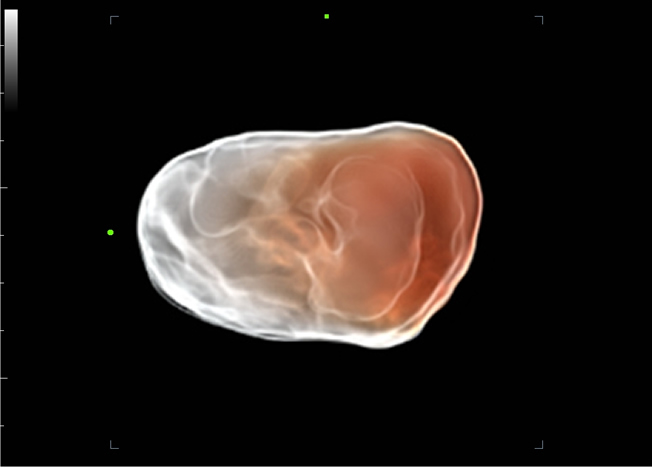

Com base em uma profunda vis?o das necessidades do cliente, o DC-70 com X-Insight foi desenvolvido para oferecer diagnĂłsticos por imagens de alta eficiĂȘncia e com precis?o, o que Ă© possĂvel gra?as Ă Nitidez eXclusiva, InteligĂȘncia eXcepcional, eXceeding Experience.

Imagens clĂnicas